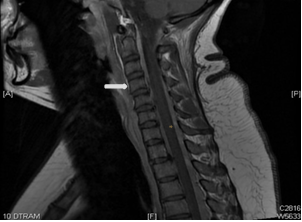

She had MRI brain and C spine with contrast, (Figure 1) a lumbar puncture after imaging, intravenous pain medication, dexamethasone per os, and was positioned supinely. Her brain MRI and C spine showed signs of low intracranial pressure with DME; see in Figure 2. She initially had a traumatic and dry LP with Glucose 5.68, raised protein of 3672 mg, 54000 red cells, 43 white cells and xanthochromia was positive.

Figure 1 white arrow pointing to contrast enhancement.

Figure 2 white arrows pointing to contrast enhancement.